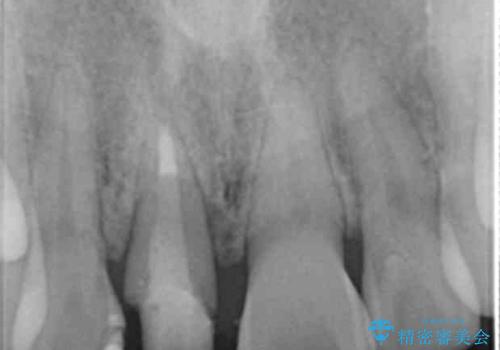

- 幼少期に前歯をぶつけて歯が折れ、神経の治療・クラウン治療を行った。グラつきと見た目の改善を希望して来院されました。

精密な仮歯をいれ、歯周組織を整えるとともにファイバーコア築盛、シェードテイキングを行い見た目に自然なジルコニアクラウンを製作していきます。